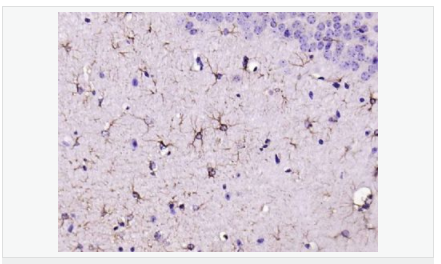

| 產(chǎn)品應(yīng)用 | WB=1:500-2000 ELISA=1:5000-10000 IHC-P=1:200-1000 IHC-F=1:200-1000 Flow-Cyt=1μg/Test ICC=1:100 IF=1:200-800 (石蠟切片需做抗原修復(fù)) not yet tested in other applications. optimal dilutions/concentrations should be determined by the end user. |

| 產(chǎn)品介紹 | This gene encodes one of the major intermediate filament proteins of mature astrocytes. It is used as a marker to distinguish astrocytes from other glial cells during development. Mutations in this gene cause Alexander disease, a rare disorder of astrocytes in the central nervous system. Alternative splicing results in multiple transcript variants encoding distinct isoforms. [provided by RefSeq, Oct 2008] Function: GFAP, a class-III intermediate filament, is a cell-specific marker that, during the development of the central nervous system, distinguishes astrocytes from other glial cells. Subunit: Interacts with SYNM. Isoform 3 interacts with PSEN1 (via N-terminus). Subcellular Location: Cytoplasm. Note=Associated with intermediate filaments. Tissue Specificity: Expressed in cells lacking fibronectin. Post-translational modifications: Phosphorylated by PKN1. DISEASE: Defects in GFAP are a cause of Alexander disease (ALEXD) [MIM:203450]. Alexander disease is a rare disorder of the central nervous system. It is a progressive leukoencephalopathy whose hallmark is the widespread accumulation of Rosenthal fibers which are cytoplasmic inclusions in astrocytes. The most common form affects infants and young children, and is characterized by progressive failure of central myelination, usually leading to death usually within the first decade. Infants with Alexander disease develop a leukoencephalopathy with macrocephaly, seizures, and psychomotor retardation. Patients with juvenile or adult forms typically experience ataxia, bulbar signs and spasticity, and a more slowly progressive course. Similarity: Belongs to the intermediate filament family. SWISS: P14136 Gene ID: 2670 Database links: Entrez Gene: 2670 Human Entrez Gene: 14580 Mouse Omim: 137780 Human SwissProt: P14136 Human SwissProt: P03995 Mouse Important Note: This product as supplied is intended for research use only, not for use in human, therapeutic or diagnostic applications. 星形膠質(zhì)細(xì)胞標(biāo)志物 (Astrocyte Marker) GFAP是一個56kDa的中間絲蛋白(intermediate filament,IF),在中樞神經(jīng)系統(tǒng)發(fā)育期是一個特異性的標(biāo)志物,以區(qū)別星形細(xì)胞和其它膠質(zhì)細(xì)胞。GFAP表達(dá)在皮層和海馬,急、慢性皮質(zhì)酮治療時表達(dá)減少。 GFAP可以和人、大鼠、小鼠的GFAP反應(yīng),在正常和腫瘤性的星形膠質(zhì)細(xì)胞陽性表達(dá),而神經(jīng)節(jié)細(xì)胞、神經(jīng)元、成纖維細(xì)胞、少突膠質(zhì)細(xì)胞和這些細(xì)胞來源的腫瘤細(xì)胞陰性表達(dá),主要用于星形膠質(zhì)瘤等中樞神經(jīng)系統(tǒng)腫瘤的診斷和鑒別診斷,GFAP的缺乏可導(dǎo)致AD病。 |